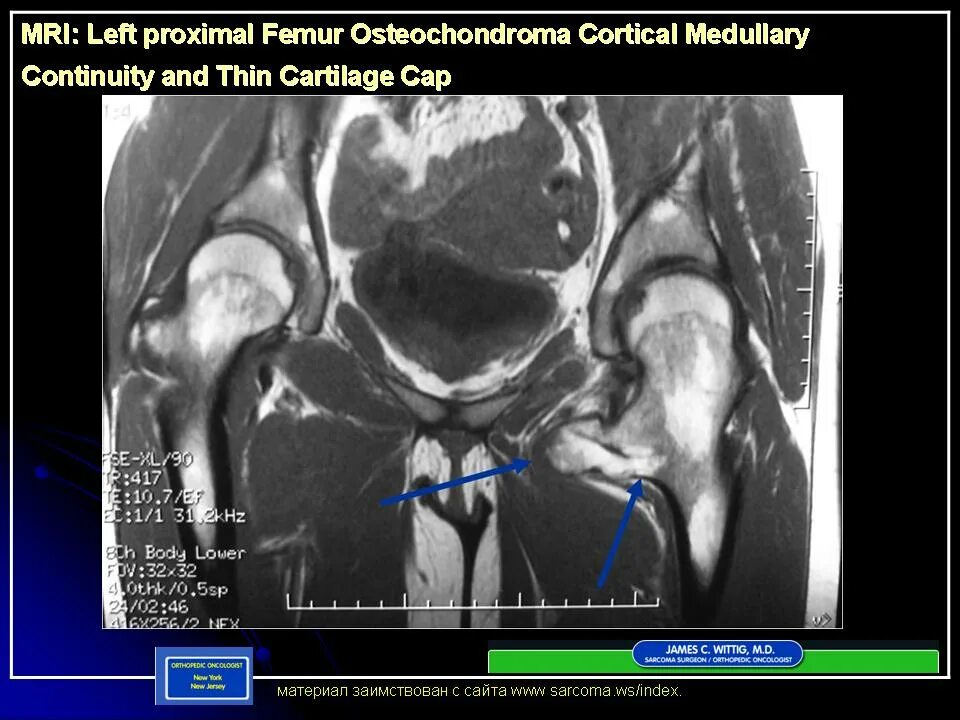

Метастазы в тазобедренном